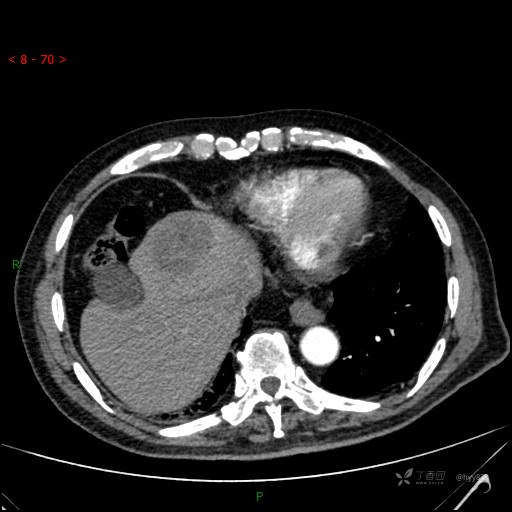

增强动脉期

img

肝脓肿 (73)